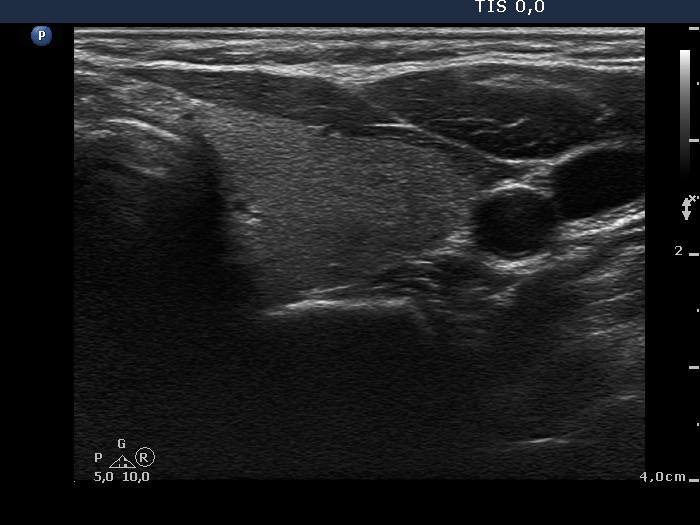

Subacute granulomatous de Quervain's thyroiditis - Case 6.

Five months after initial examination (ultrasonographic picture 6)

Left lobe, horizontal scan. The lobe is intact.